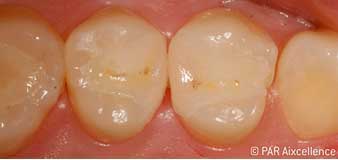

Рис. 1. Начальный вид зубов без клинических признаков кариеса